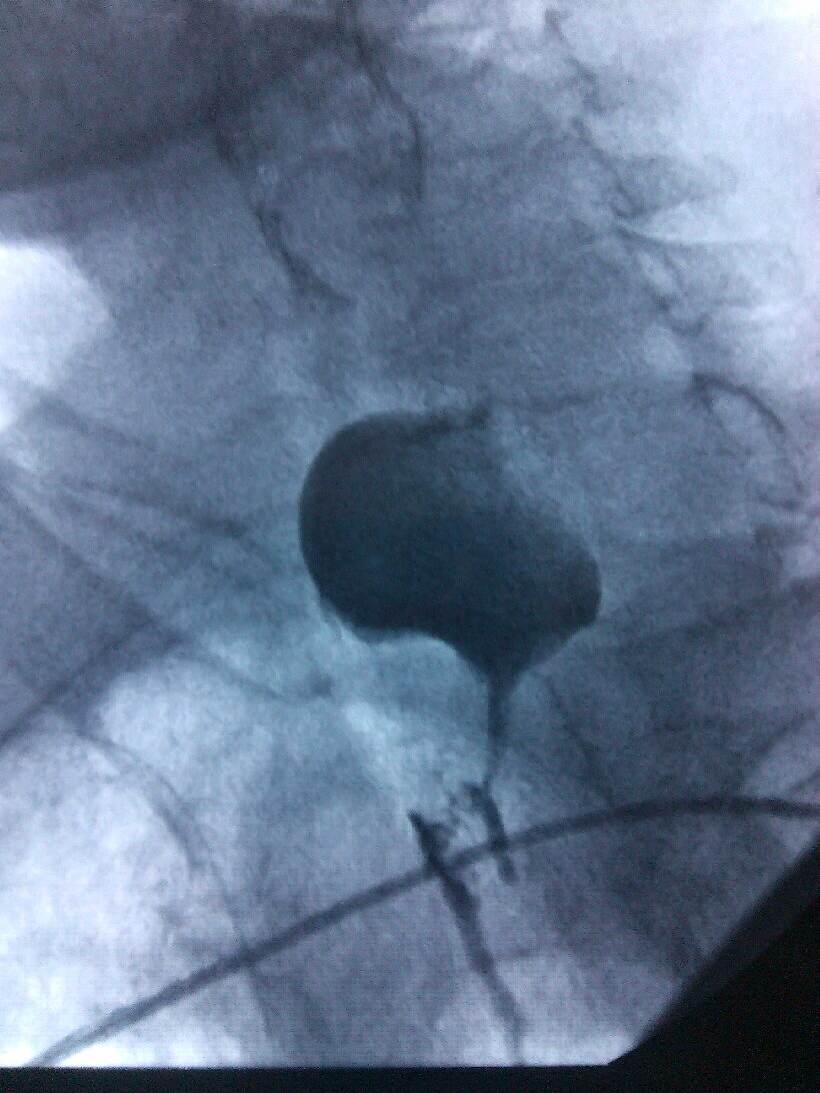

根据病人的的身体条件,无法采用手术、放疗、化疗进行治疗。肿瘤科主任、副主任医师熊小平组织医生详细分析患者的病情,找到病因所在,制定周密的治疗方案,运用食管支架植入法将食管扩张,这样既解决了患者的“吃饭”问题,又解决了分泌物排流的问题,减轻了患者的痛苦,提高了生活质量。患者及家属非常感激,多次口头表示感谢:“没想到跳蛋视频